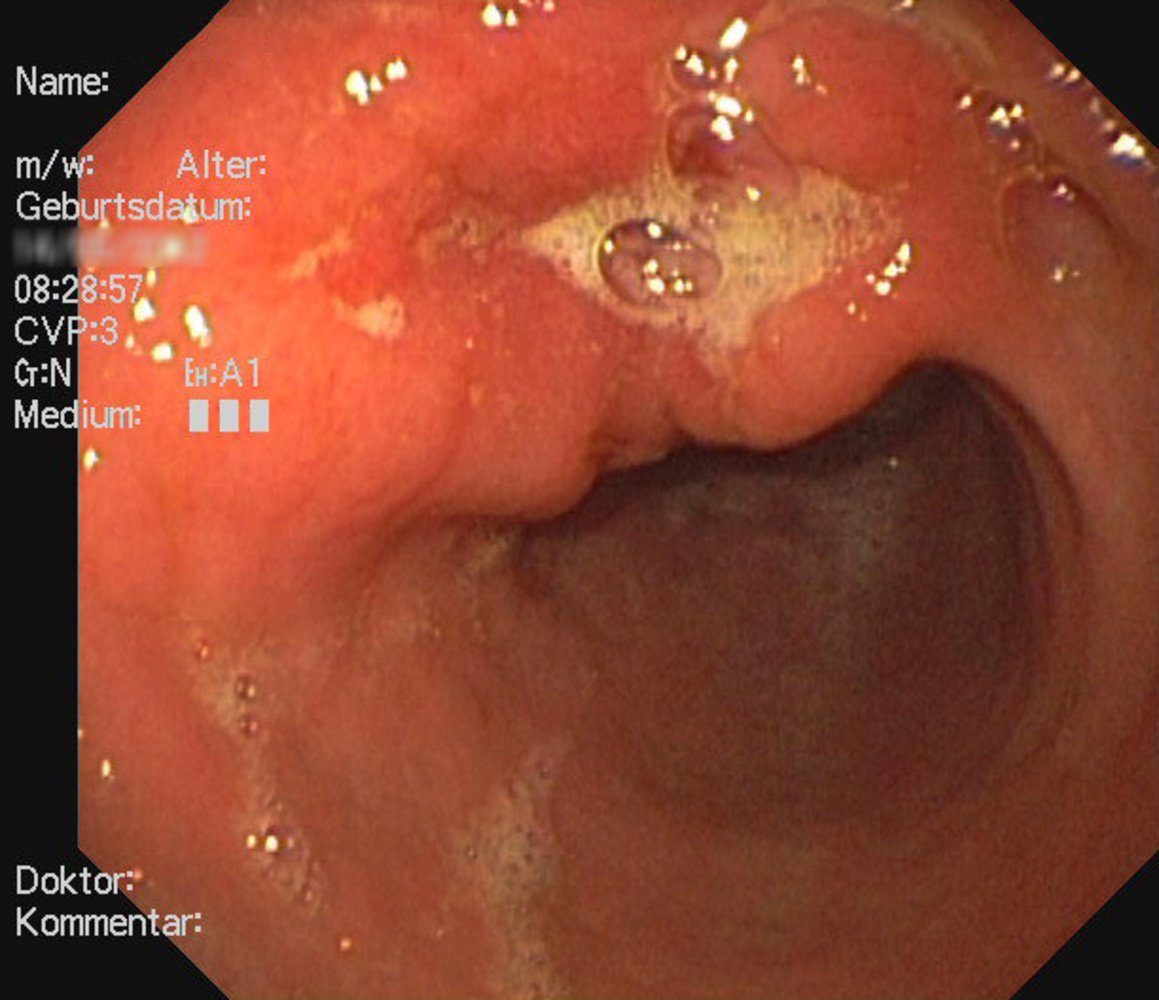

Endoscopy view of the gastric antrum

There is a gastric mass at the level of the lesser curvature with an irregular margin (perimeter marked by green outline) and central ulceration (green overlay).

These findings are consistent with gastric cancer.